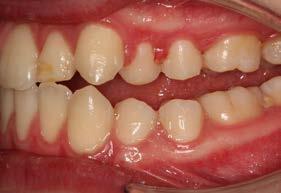

Figura 3. Lateral derecha. Figura 4. Izquierda de inicio. Figura 5. Frente. Figura 6. Overjet, laterales derecha e izquierda.

Se presenta un paciente en edad de 15 años y 2 meses. Refiere que acude a consulta por evaluación. En la valoración extraoral presente la hiperdivergencia y sus posiciones dentales (Figura 1), tiene un perfil convexo con hiperactividad del músculo mentoniano e incompetencia labial, y en la radiografía lateral de cráneo inicial (Figura 2) se aprecia el patrón esquelético clase II severo.

Las fotografías intraorales muestran las relaciones molares clase II y las relaciones caninas clase II bilaterales (Figura 3 y 4), espaciamiento anterosuperior, un overjet y overbite aumentado (Figura 5). La forma de los arcos es cuadrada, superior e inferior, con el apiñamiento moderado inferior y los espacios en superior.